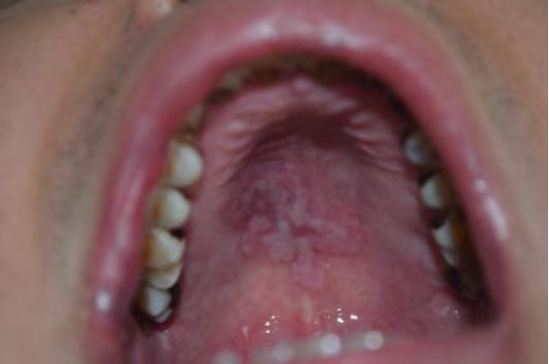

梅毒患者口腔

HIV患者毛状白斑伴真菌感染

传染病包括HIV、梅毒、丙肝、乙肝都是非常普遍的极具传染性的传染病可能通过密切接触、母婴、血液和性传播。密切接触传播途径包括阳性者的创伤出血污染环境、共用牙刷、口杯、毛巾等。

若在诊疗前,抽血检查出患者传染病结果阳性,临床医生将会安排单独的诊室为患者诊疗,在诊疗结束,患者离开诊疗区后,医务人员将根据传染病的传播途径,科学、及时的对物体表面和空气进行终末消毒,严格落实消毒隔离管控,避免了医护人员、其他患者及患者家属的感染风险,为下一个就诊患者提供安全可靠的就医环境。